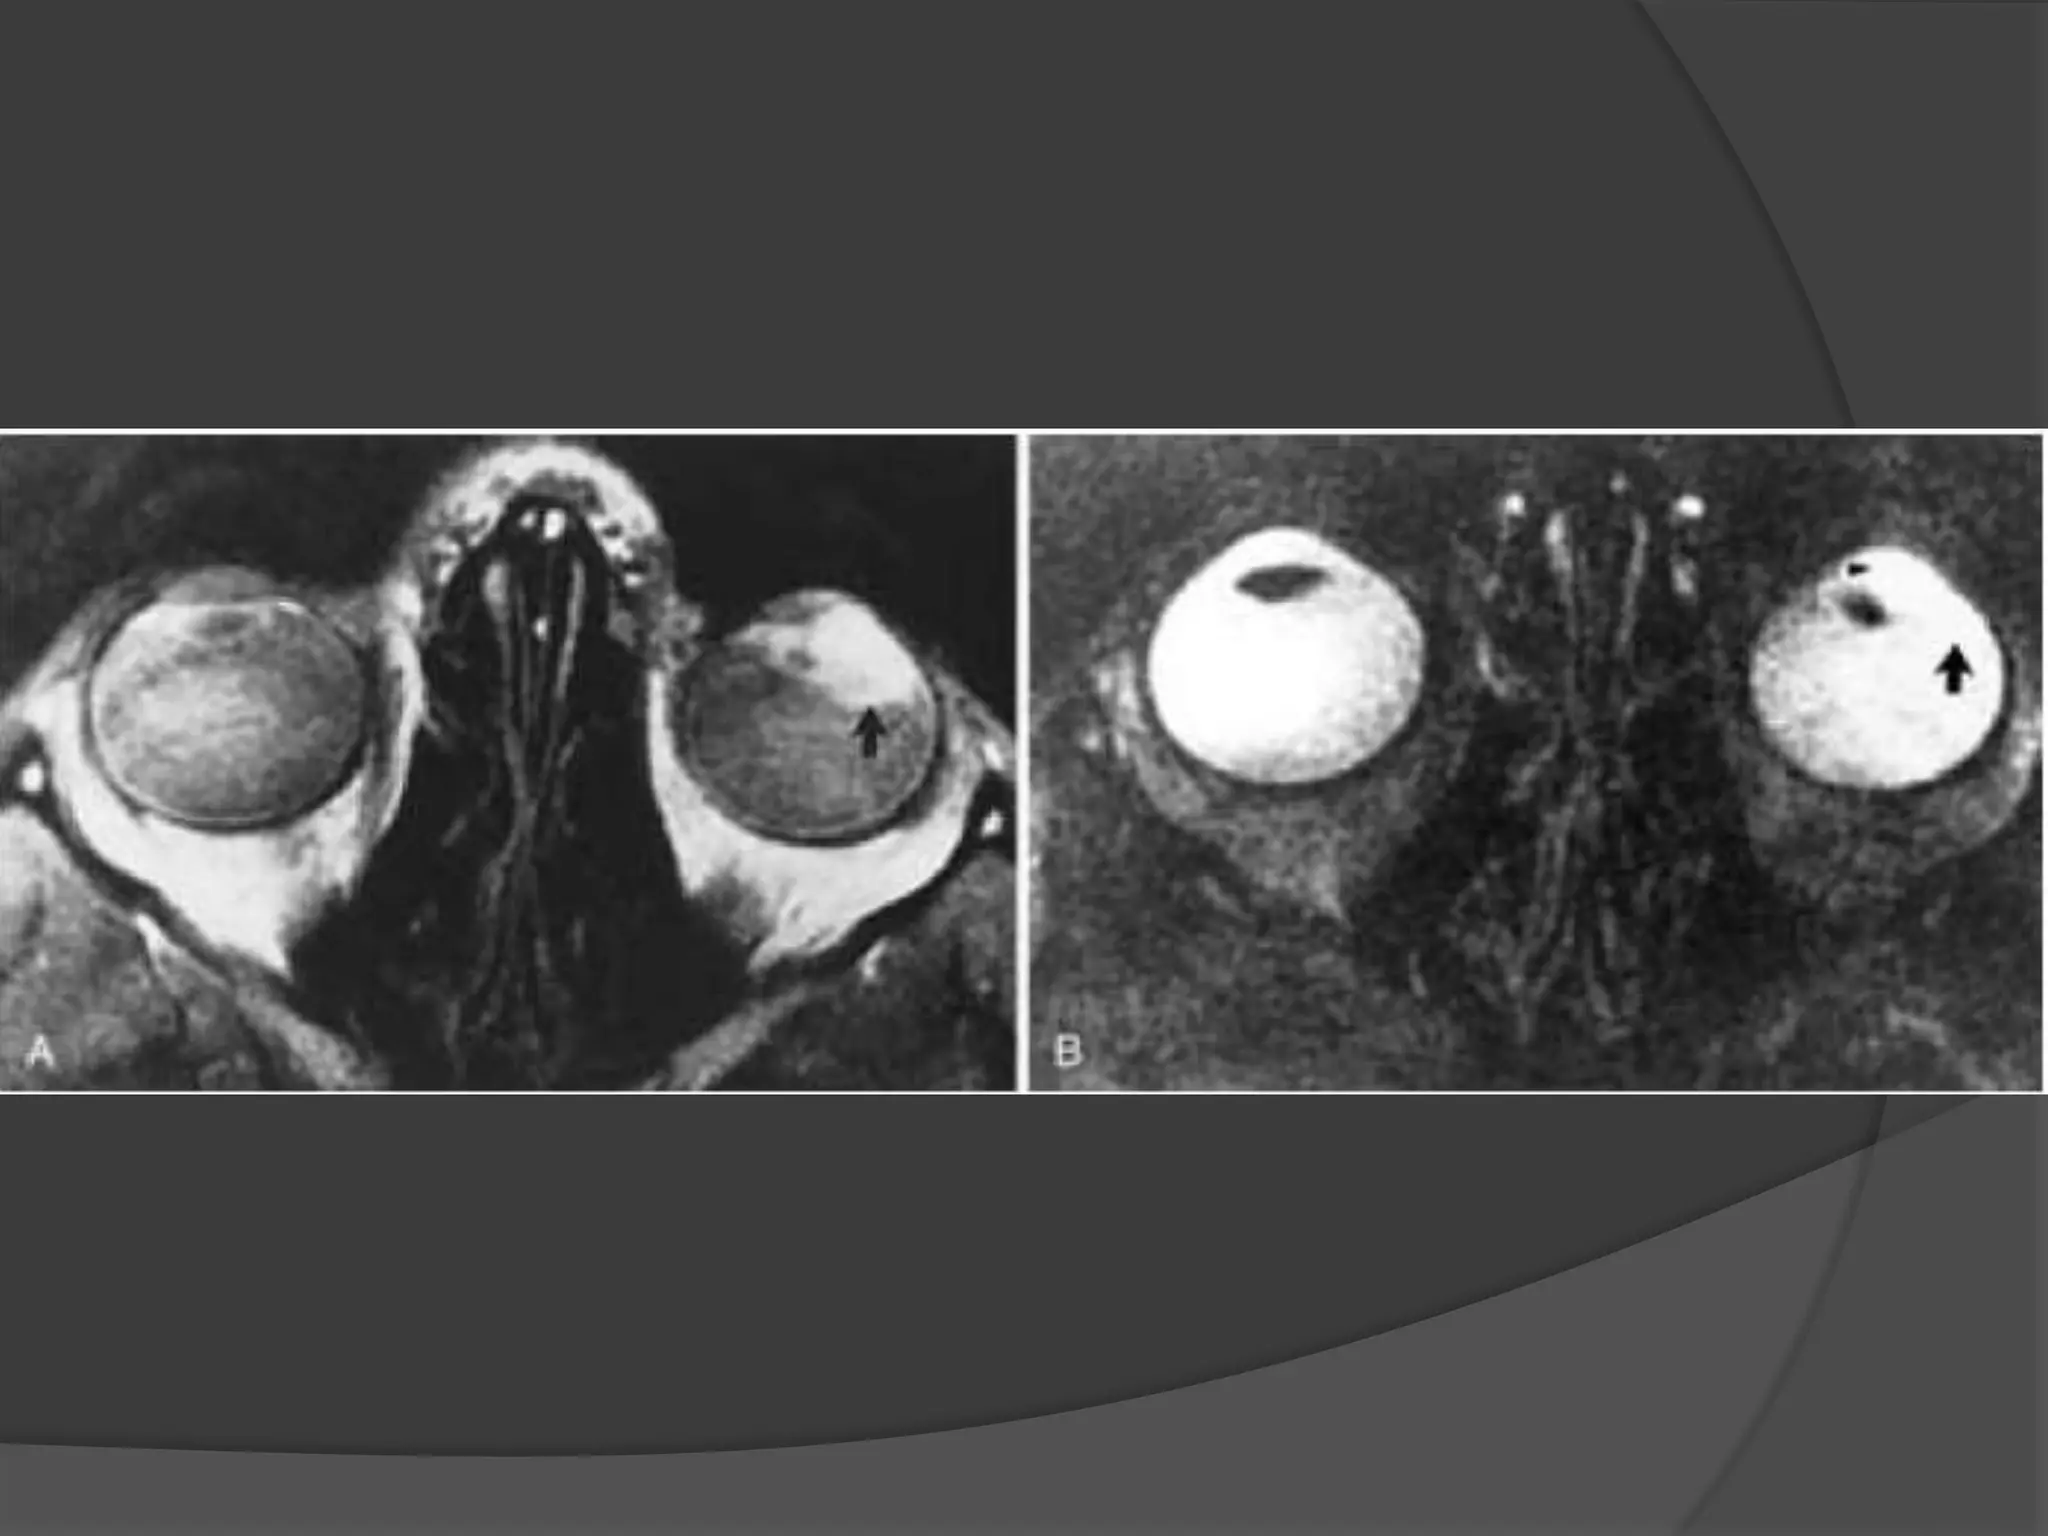

Imaging : MRI is the modality of choice with hyper intense signal of

T2WI due to fluid and edema. Fat Sat contrast enhanced T1WI will show

areas of demyelination. CT relatively insensitive.

Optic Neuritis. CE Fat Sat T1W axial

(B) MR images demonstrate subtle enlargement and enhancement of the left

optic nerve (curved arrow).

T 2 WI (C) demonstrates corresponding increased signal intensity (straight

arrow).